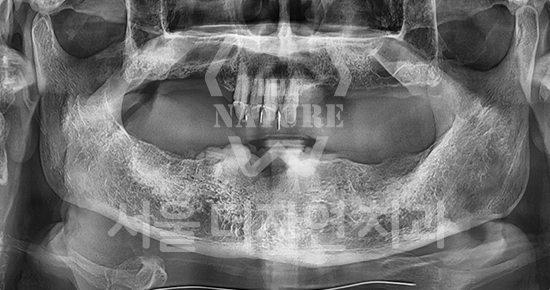

#상악동 거상술

-

BEFORE: 2021.02.01

AFTER: 2021.05.13